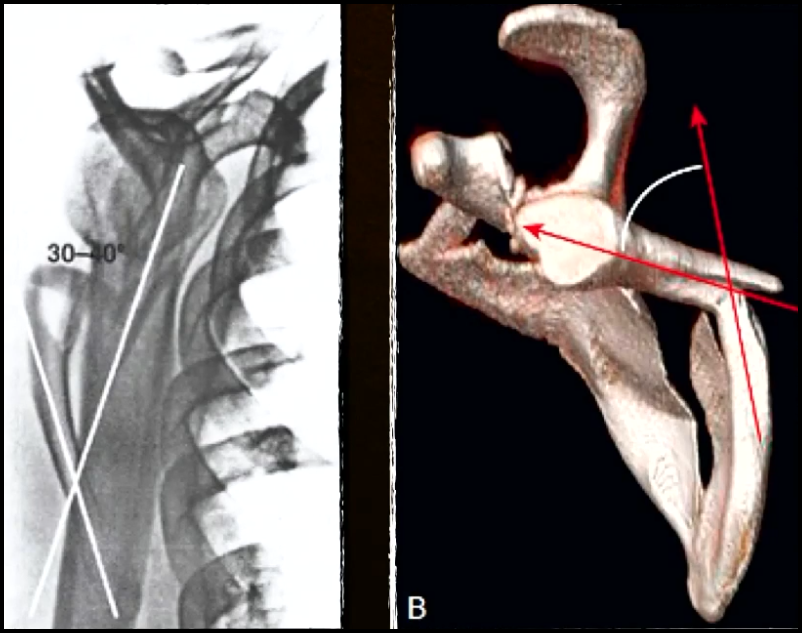

Avaliação desvio angular ?

Ângulo entre os eixos longos dos fragmentos.

Aceitável se < 30 - 45º